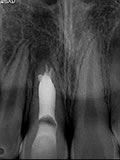

症例 17. 内部吸収

上顎右側中切歯の口蓋部にパーフォレーションを伴う内部吸収症例

治療前